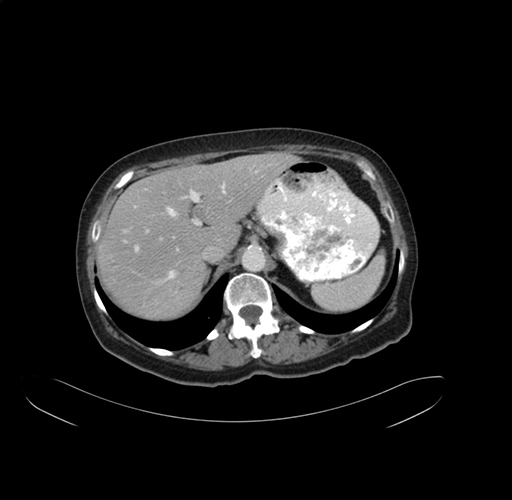

Pre-Chemo: Axial Venous

Axial Venous